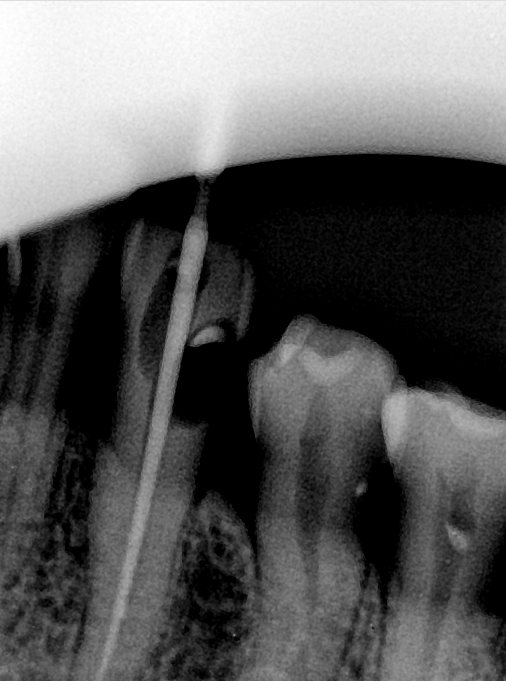

CR/DR 牙齿分割阶段记录

当前进展

- 完成了 CR/DR 牙齿相关分割训练

- 当前结果已经达到阶段预期,但仍有细节问题需要继续处理

相关测试

遇到的问题

- 训练过程中出现过 mask 下移问题

- 部分结果会出现 box 填充异常

- mask 边缘仍然有比较明显的锯齿感